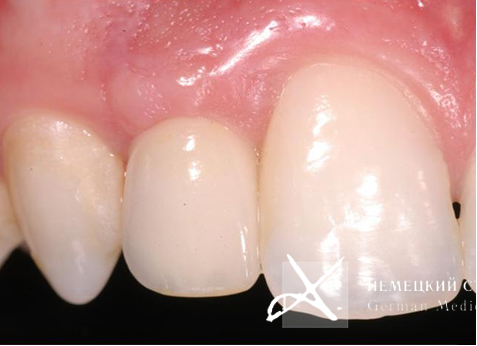

Для устранения эффекта серой, синюшной десны выполнены эстетические безметаллловые оксидциркониевые реставрации. Представленные рентгенограммы демонстрируют успешную имплантацию и максимальную точность прилегания конструкции, а иллюстрации после окончания лечения убеждают в гарантированном достижении желаемого эстетического результата, в частности в наиболее сложной с точки зрения геометрии эстетики десневой зоне.